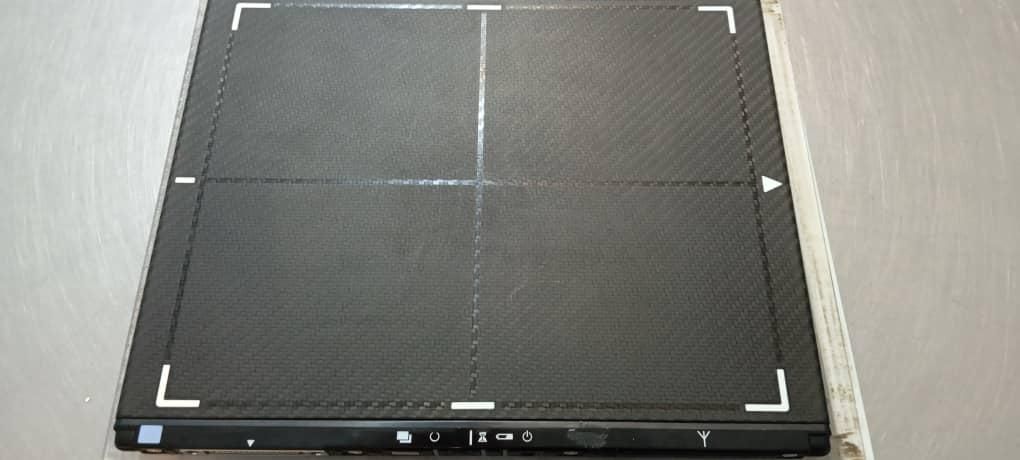

دستگاه رادیوگرافی سیار - رادیولوژی پرتابل دیجیتال EPX 2400 کره ای دارای Gen number با مجوز انرژی اتمی کاست دیجیتال DR 10*12 - فلت پنل وایرلس کونیکا مینولتا Konica Aerodr ژاپنی همراه با لب تاپ Acer مانیتور لمسی هر دو سالم و در حال کار در یک مرکز، به علت تغییر رویکرد ایده آل برای رادیولوژی پرتابل در منازل و بیماران (رادیولوژی سیار منزل)، به صورت ثابت و پرتابل برای مراکز پزشکی و دامپزشکی